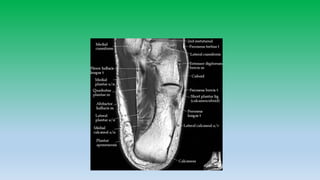

Normal Ligamentous anatomy:

• On MRI ligaments appear as a thin low signal intensity structure

between adjacent bones , becoming apparent due to adjacent high

signal fat.

• Many of the ligaments appear heterogenous due to interposition of

fat especially the posterior talo-fibular ligament and tibio-talar

component of deltoid ligament.